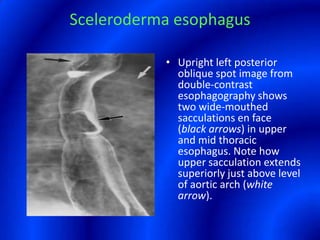

This document provides information about a barium swallow procedure. It begins with an introduction and overview of the embryology and anatomy of the pharynx and esophagus. It then describes the procedure itself, including preparation, technique, views obtained, and indications. Specific conditions that may be examined include pharyngeal and esophageal webs, foreign body impaction, scleroderma, dysphagia, mediastinal masses, and carcinoma. Diagrams are provided to illustrate normal anatomy and various pathological findings.